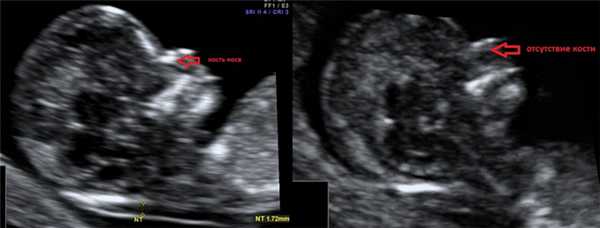

1. Увеличение ТВП.

Оценка этого параметра проводится в первое скрининговое УЗИ (11-14 недель)

2. Гипоплазия\аплазия костей носа.

Гипоплазия костей носа - уменьшение размеров косточки носа в зависимости от КТР вашего малыша.

Аплазия костей носа - отсутствие визуализации косточки носа у вашего малыша.

Отсутствие видимости костной части спинки носа у плода или ее недоразвитие (недостаточно яркая) на первом скрининге связана с задержкой отложения кальция. Такая ситуация несколько чаще может встречаться у плодов с синдромом Дауна, однако важно, что:

- само по себе отсутствие костей носа на УЗИ не является аномалией развития; может встречаться у абсолютно здоровых плодов (в 3% случаев);